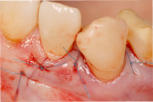

1. Regenerative Parodontaltherapie: Bei einem besonders schweren Verlauf der Parodontitis können sog. Knochentaschen und Furkationsbefall entstehen. Informationen zu Knochentaschen finden Sie unter diesem Link: Bei fortgeschrittem Knochenabbau durch Parodontitis entsteht oftmals ein sog. Furkationsbefall. Mehr Infos zum Furkationsbefall gibt es unter diesem Link:

Bestimmte Knochentaschen und bestimmte Formen von Furkationsbefall lassen sich durch spezielle parodontal-chirurgische Behandlungen regenerieren.